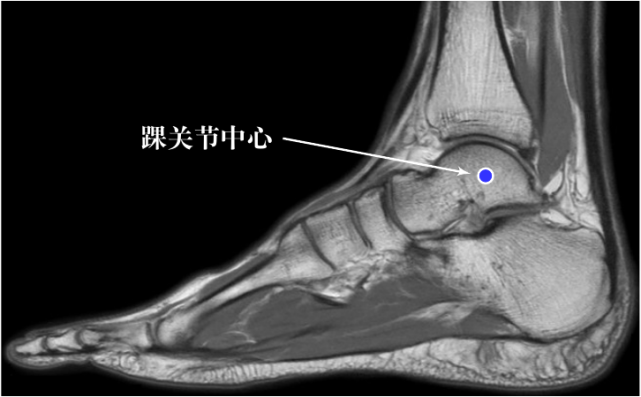

当人体的脚在做足底屈或足背屈时,脚基本上是在绕踝关节中心旋转(图 7),且旋转中心几乎不变(图 8)。

图片